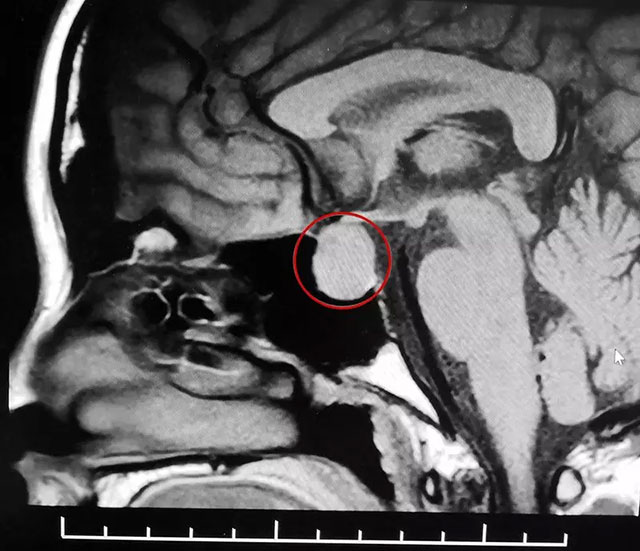

后來(lái)一位有經(jīng)驗(yàn)的醫(yī)生提醒她去檢查一下頭部,經(jīng)頭顱磁共振檢查,鞍區(qū)MRI平掃+增強(qiáng)顯示,蝶鞍顯著擴(kuò)大,鞍區(qū)見(jiàn)不規(guī)則腫塊影,大小約1.4*1.7*2.2cm。劉女士被診斷為垂體大腺瘤(垂體瘤超過(guò)1厘米就是垂體大腺瘤)。

▲ MR影像檢查顯示:垂體大腺瘤,超蝶鞍生長(zhǎng)